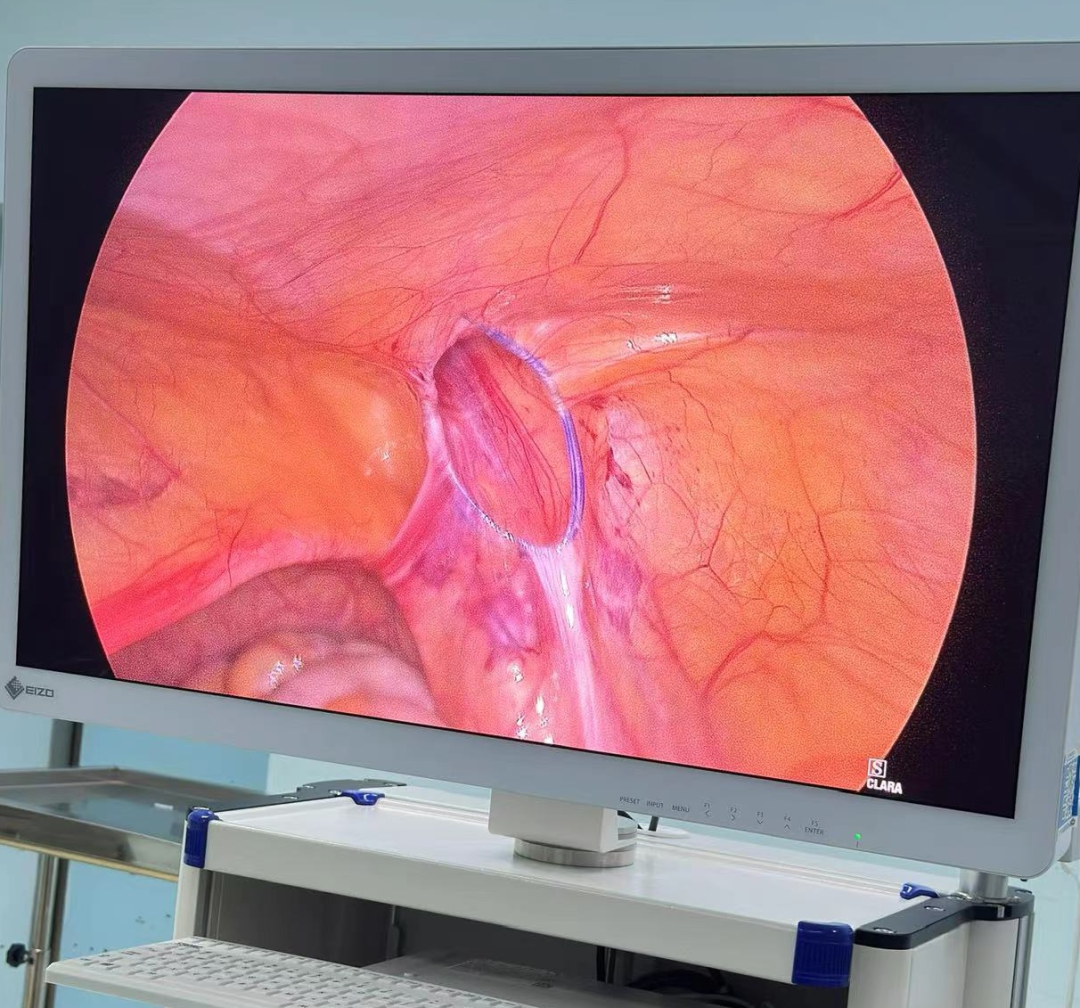

诊室里,经常能看到这样的画面:家长抱着哭得小脸通红、怎么哄都停不下来的宝宝,急急忙忙冲进来,“医生!快看看!孩子大腿根这里突然鼓了个包,越来越大!这可怎么办啊?!”——这种让人揪心的紧急情况,很多都是“小儿疝气”(俗称“小肠气”)惹的祸! 什么是小儿疝气? 简单说,就是宝宝肚子上有个“小洞洞”没长好(发病率为1%-4%),医学名称叫“腹股沟疝”,是小宝宝(尤其是男宝)很常见的一种情况。 为啥会这样?宝宝在妈妈肚子里时(先天性),腹股沟那里有个通道(学名叫“鞘状突”)本该自己关上的,但没关严实,就成了个“小洞洞”。当宝宝使劲哭闹、咳嗽、或者用力便便时,肚子里压力一大,一小段肠子或者组织就可能从这个“小洞洞”钻出,鼓起一个“包”。 最典型的表现:宝宝大腿根附近,出现一个“鼓包”,而且这个包在宝宝安静或躺平时,常常能自己缩回去(或者家长轻轻一推就能推回去)。 家长最关心的问题 1.必须要做手术吗? 在1岁以内有长好的可能,可以观察看看。超过1岁还没好,或者包块反复卡住(嵌顿)引起剧痛,千万别等了,尽早做手术,最佳手术年龄通常是1到3岁。 2.麻醉会不会伤脑子? 手术用的是全身麻醉,目前全球尚无研究证实规范全麻操作会影响智力或记忆力。宝宝就像睡了一个很沉很沉的觉,手术过程中完全没感觉、也不会记得。 为什么腹腔镜修补术比较适合宝宝? 传统开刀手术需在大腿根附近切开一个3厘米左右长的口子,手术后会留下挺明显的疤,恢复也慢。 腹腔镜修补术是通过肚子上3-5毫米(米粒般的大小)的小孔进行手术,同时能探查并处理对侧“隐性疝”,一次手术就搞定,不用再挨第二刀。术后一般6-8小时可以下床,24小时后能出院。 术前术后,家长这样配合更安心 术前准备 1.手术前6到8个小时别让孩子吃东西、喝水,防止打麻药时吐出来呛到。 2.按医生要求做抽血、凝血这些检查,看看孩子身体适不适合手术。 3.手术前一天给孩子洗个澡,把肚脐和大腿根附近洗干净。 4.多哄哄孩子,别让他哭得太厉害(哭狠了肚子里压力大,对手术不好)。 术后护理 饮食:术后6小时可少量喂水,无呕吐可逐渐恢复正常饮食。 活动:术后一周避免剧烈跑跳、哭闹或用力排便,防止腹压过高。 伤口护理:保持伤口清洁干燥,若发现红肿、渗液等不适,及时联系医生。 注:部分图片来源于网络,如有侵权,请联系删除。 贵州航天医院普外科专家简介 高大勇 普外科(肛肠外科)学科带头人、名誉主任,主任医师、教授 临床擅长:对中西医结合诊治肛肠学科各种常见病、多发病及疑难杂症等具有丰富的临床经验。 原遵义市第一人民医院(遵义医科大学第三附属医院)、遵义市中医院肛肠科主任。中华中医药学会肛肠分会常委,全国中医肛肠学科名专家,中国健康促进与教育协会肛肠分会常委,中国康复医学会肛肠疾病康复专业委员会常委,中国民间中医医药研究开发协会肛肠分会副秘书长,中国医师协会中西医结合肛肠医师专业委员会常委,国家二级心理咨询师,贵州省第一批中医名医工作指导老师,遵义市名中医,遵义市肛肠学会会长,遵义市肛肠质控中心名誉主任,遵义市中西医结合学会名誉会长,遵义市健康科普专家,原贵州省中西医结合学会肛肠分会副主任委员、贵州省中医肛肠质控中心副主任、遵义市医学会医疗鉴定委员会专家、遵义市卫生系列高评委。发表论文30余篇,主编和参编医学著作5本,主持省级科研课题2项、市级科研课题2项、院级科研课题1项。 梁 跃 中共党员,普外科党支部书记、主任,主任医师 临床擅长:对普外科各类肿瘤手术具有丰富的临床经验。 毕业于遵义医学院,遵义市医学会小儿外科学分会常务委员,遵义市肛肠协会理事,遵义市医学会核医学分会(第二届)委员会委员;荣获第三期“黔医人才计划”优秀学员称号;主持市级课题1项,完成省级课题1项,在国内各类刊物上发表论文10余篇。 钱科洪 民盟盟员,普外科副主任医师 临床擅长:从事普外科临床工作30余年,对各类普外科疾病的诊治、乳腺、甲状腺、胃十二指肠、结直肠等疾病及疑难杂症具有丰富的临床经验。 毕业于遵义医学院临床医疗系,2009年前往中山大学附属第一医院微创外科进修学习,在国内各专业期刊发表论文数篇。 贵州航天医院普外科简介 基本情况 贵州航天医院普外科成立于1968年,前身属于航天部O61基地3417医院外一科,1998年3417医院、3427医院合并后更名为普外科,下设胃肠外科、肛肠外科2个亚专业科室,拥有在全市较为先进的专科设备和技术,是中国疝病专科联盟单位,贵州医科大学附属医院胃肠外科专科联盟单位。开放床位40张,配备医护人员21人。 专科特色 普外科致力于胃肠及肛肠疾病的外科临床诊治及科研,以腹腔镜微创外科技术为本,形成以快速康复治疗胃肿瘤、结直肠肿瘤、小肠肿瘤、直肠脱垂、肥胖病、急腹症、各类疝、痔、瘘等专科特色,同时注重胃肠疾病尤其是结直肠恶性肿瘤的基础研究和临床转化研究,总体诊断和治疗水平在区域同级医院居于领先水平。 开展手术:腹腔镜下胃癌根治术,腹腔镜下袖状胃切除术,腹腔镜下胃肠道间质瘤切除术,腹腔镜下结、直肠癌根治术,胃癌、结直肠癌的精准治疗,腹腔镜下小儿疝气、成人疝修补术,腹腔镜下阑尾手术,内痔的硬化注射治疗及痔疮的微创治疗:ATH、PPH、TST,直肠脱垂的各种手术治疗,难治性伤口VSD技术,鼻胃肠管、肠梗阻导管置入术,肛肠术后间歇性导尿技术,并引进了中医适宜技术,也为各种化疗患者提供输液港安装,提高患者就医体验。 腹腔镜下腹股沟疝 无张力修补术 腹股沟疝里金斯坦(Lichtenstein)手术 PPH微创术治疗环状混合痔 黏连性或炎性肠梗阻-肠梗阻导管 腹腔镜袖状胃切除 腹腔镜阑尾切除术 腹腔镜阑尾肿瘤切除术 腹腔镜下结肠癌根治术 诊疗范围 胃肿瘤、结直肠肿瘤、小肠肿瘤、肥胖症、各类急腹症、腹部外伤、腹壁疝、便秘、直肠脱垂、痔疮、肛瘘、肛裂等胃肠、肛肠外科疾病。 END